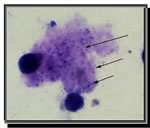

Come fare la diagnosi?

La diagnosi definitiva richiede l’isolamento del PC.

Diagnosi diretta

- Induzione sputo sensibilità variabile 50-90% (in una metanalisi sensibilità 55%). *Non consigliato nel paziente compromesso (aumenta le secrezioni).

- Lavaggio broncoalveolare (BAL): sensibilità 90%.

Esistono diversi tipi di colorazioni:

- Colorazione di Grocot e blu di toluidina per le forme cistiche

- Giemsa o altre colorazioni policromatiche per le forme trofiche

- IFA per entrambe le forme (cisti e trofozoiti). 23,34

PCR su aspirato orofaringeo: sensibilità 89%, specificità 94%.